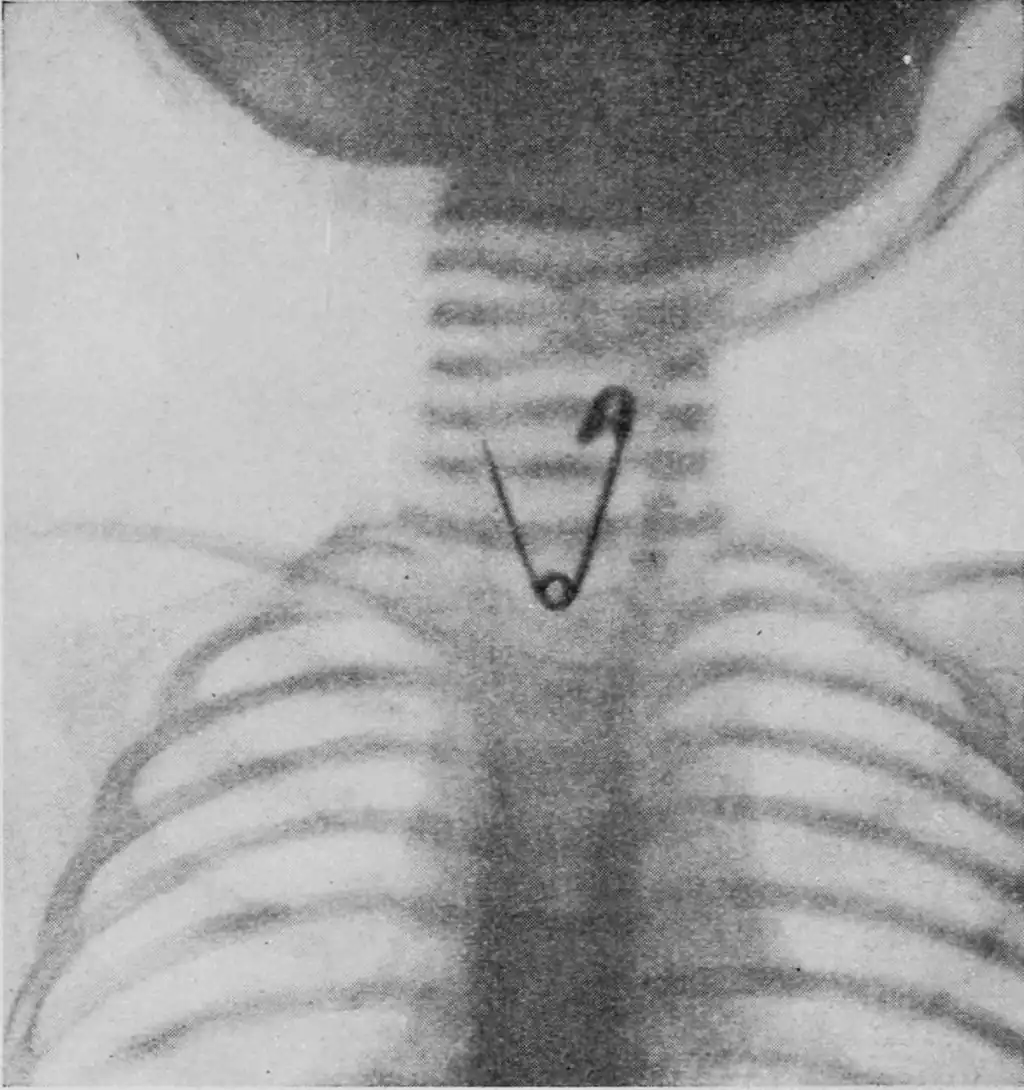

X-Ray Finds Safety Pin in Baby's Throat

REMOVING an open safety pin which was swallowed by a seven-months-old baby with the sole aid of X-rays and a snare, was the remarkable operation recently performed by Dr. G. S. Otrich, of Belleville, Ill.

This open safety pin was extracted with a snare by the aid of the X-ray and a fluoroscope

When an X-ray photograph was taken of the child, it was discovered that the open pin was lodged in the esophagus, with the point sticking upward towards the child's mouth. The X-ray tube was arranged beneath an ordinary table, so as to throw the light upward, and the child placed so that the light from the tube would be in a direct line. A fluoroscope was adjusted directly over the child, and the obstruction became clearly visible. The doctor passed a small snare into the esophagus, and with infinite care passed it slightly beyond the pin. After withdrawing it until the pin seemed to be engaged, he closed the snare. On the first attempt the pin was closed and withdrawn.